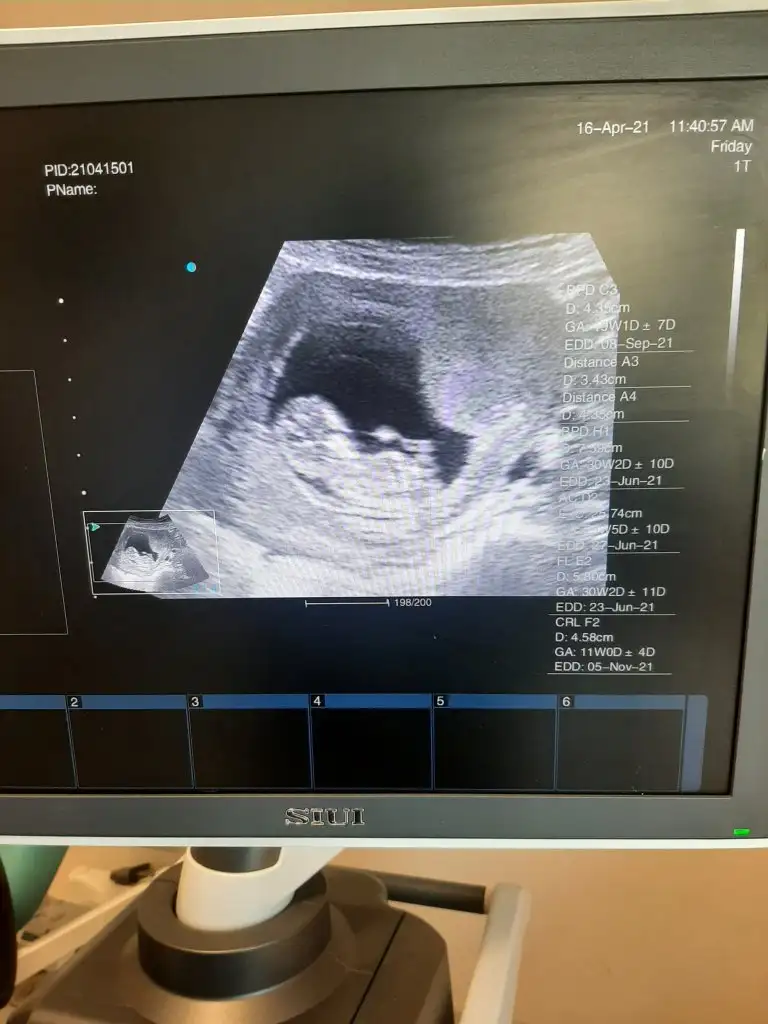

Rica etsem usg mize bakabilir misinizEmin olamadımkız olabilir

Erkek sanki11+5 haftalık rica etsem bana da tahminde bulunur musun ?

Erkek sanki emin olamadım başka USG varsa paylaşın